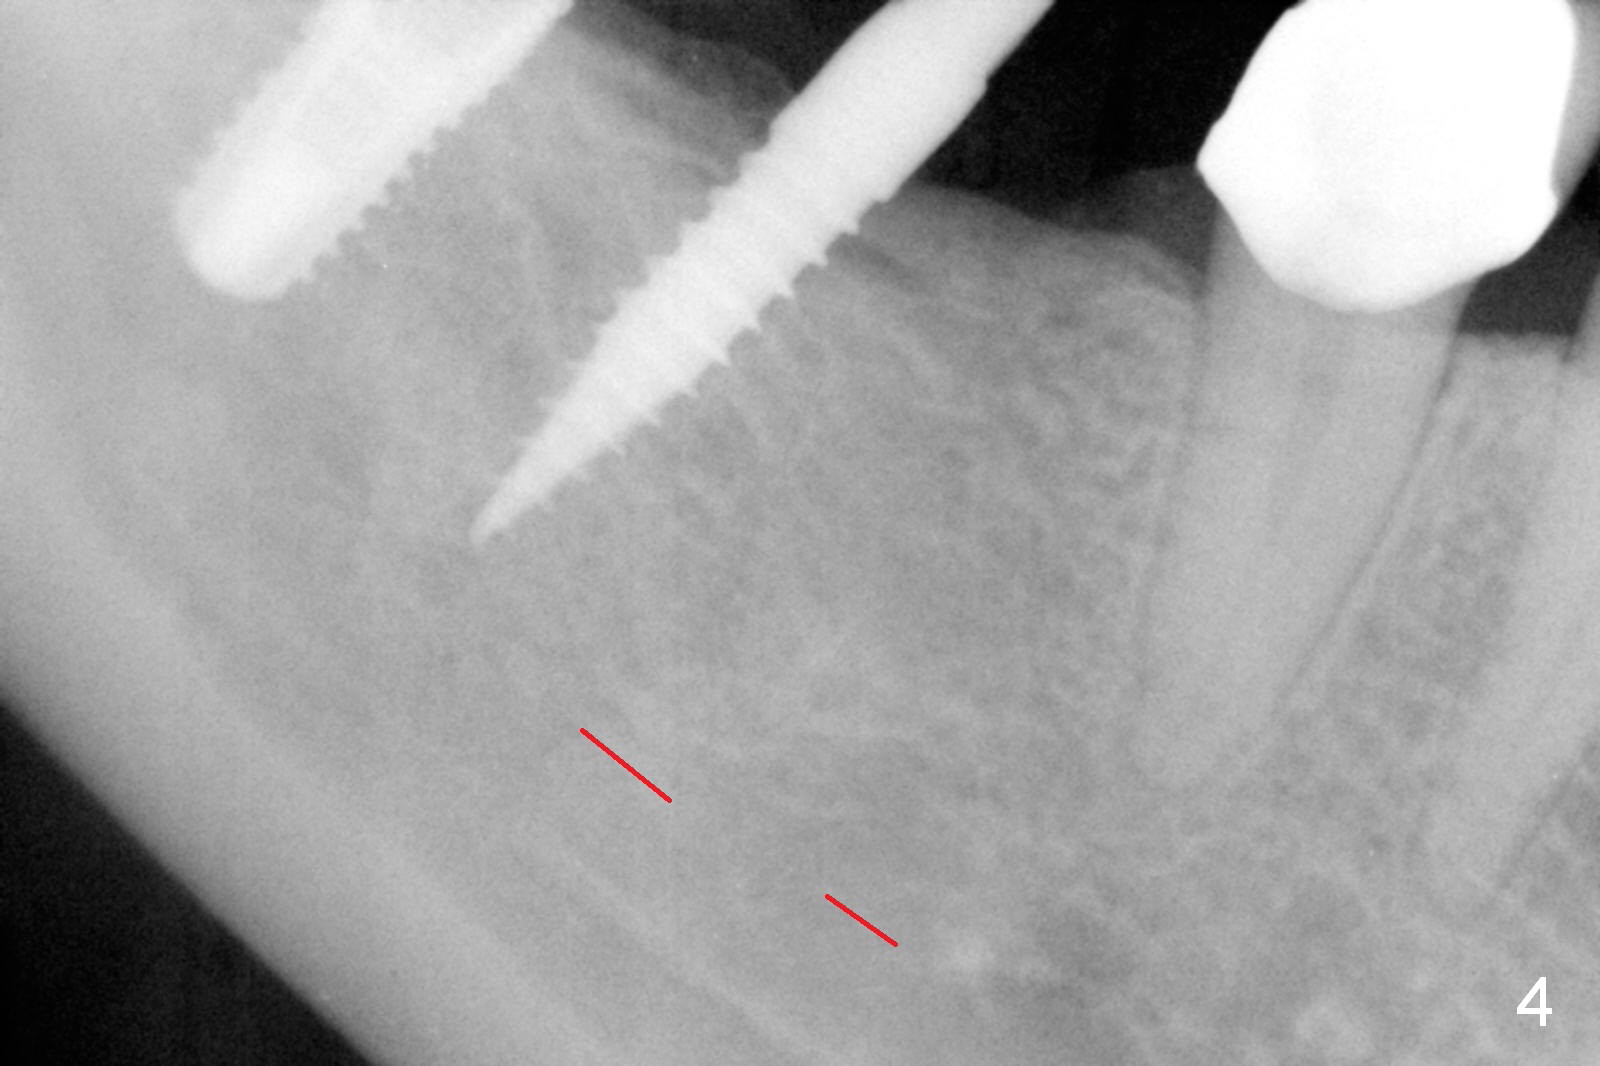

The patient returns for final restoration 3 months postop; bone resorption around the 1-piece implant is minimal (Fig.7).  The definitive restoration is also splinted.  The latter is further justified when the implant at #30 is found to be distal prior to cementation (Fig.8 *).  It appears that implant spacing at the root level is more critical than parallelism, as compared to Fig.7.  Let us improve this aspect.  Bone loss around the implants remains minimal 7 months post cementation (Fig.9).  It is the same 1 year 8 months post cementation (Fig.10), as compared to a cantilever FPD on the other side (Fig.11).  The bone density around the implants at #30 and 31 increases 2 year 8 months post cementation (Fig.12).